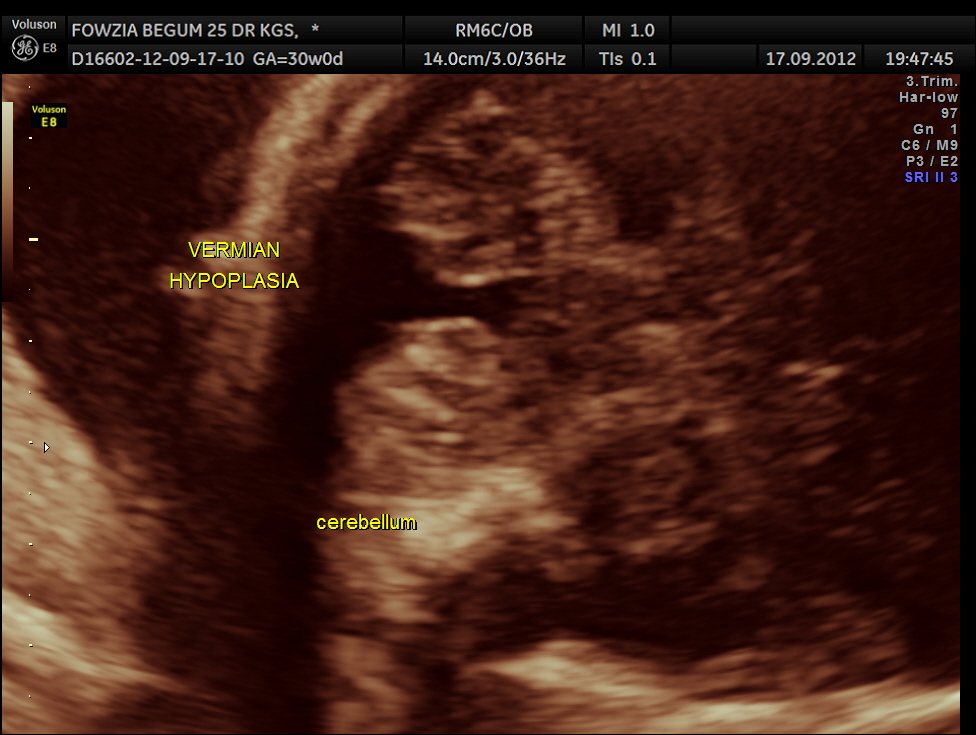

Ultrasound pictures of the fetal cranium are given below and showed cerebellar vermian dysgenesis .The buttocks sign can be appreciated.